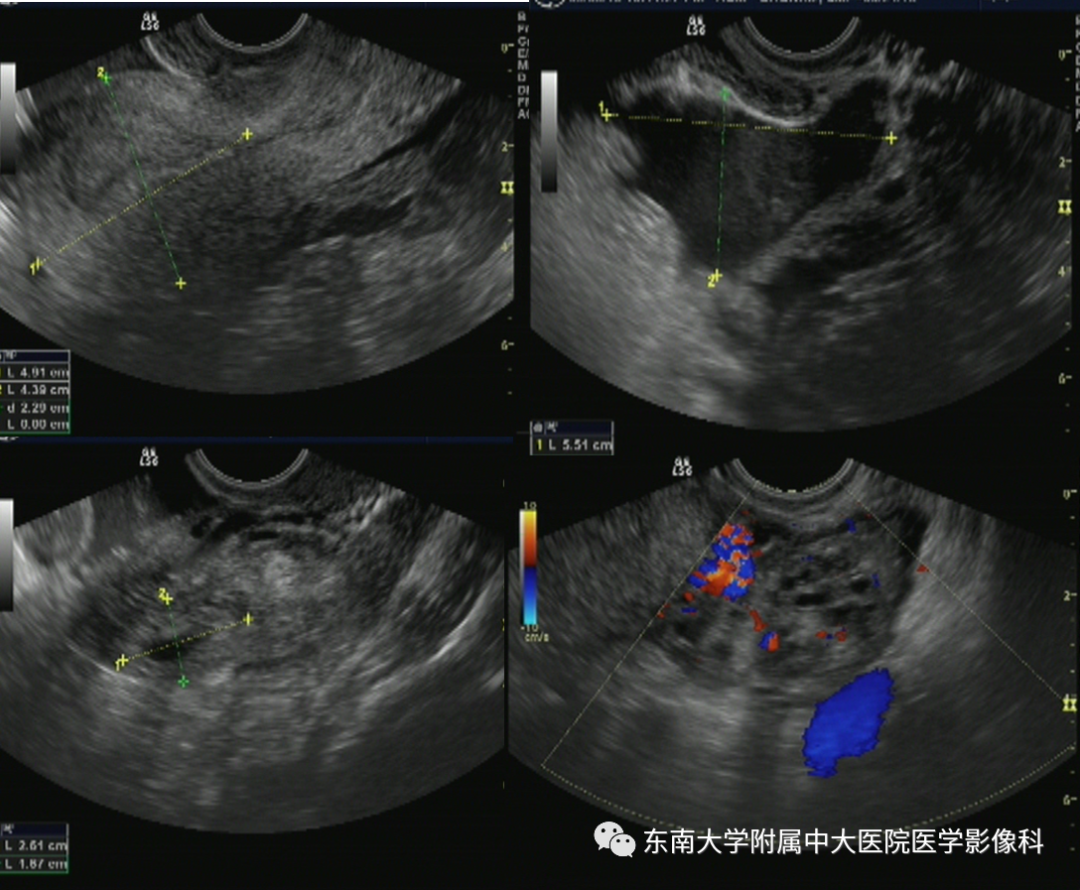

病史

女,24岁,因“停经42天,下腹痛3小时”入院

影像学表现

超声

病例结果:宫外孕破裂